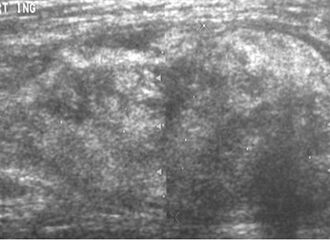

قد لا يكون التصوير بالموجات فوق الصوتية قادراً على التمييز بين الغرن الشحي والورم الشحمي الحميد، وبالتالي، فإن التصوير بالرنين المغناطيسي هو التصوير الأولي المفضل.[4]

Medical ultrasonography of a liposarcoma: In this case a heterogeneous mass consisting of an upper hyperechoic portion, corresponding to lipomatous matrix, and areas of hypoechogenicity corresponding to nonlipomatous components.[5]

Ultrasonography of a liposarcoma mimicking a lipoma. A homogeneous hypoechoic mass presenting with the same appearance of lipoma. It was clinically distinguished as having rapid growth.[5]